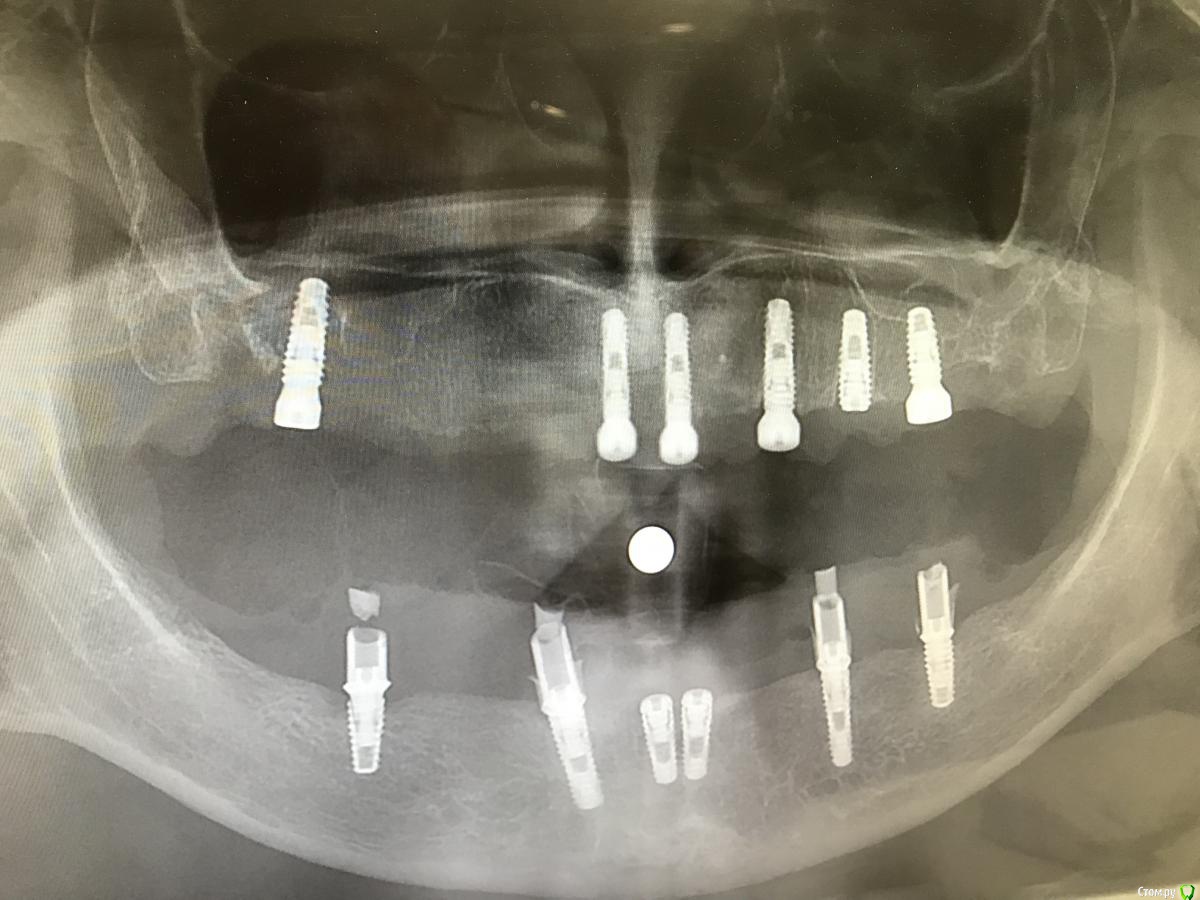

alekcandr ovs. Опубликовано 6 мая, 2018 Поделиться Опубликовано 6 мая, 2018 (изменено) Дорогие коллеги, что посоветуете по материалу изготовления постоянных конструкций??? В.Ч не съёмное и Н.Ч не съёмное и комбинации условно съёмные!!! Особенно В.Ч 1 сегмент! К сожалению в 1 сегменте от пластики кости пациент на отрез отказался!!! Спасибо! Изменено 6 мая, 2018 пользователем alekcandr ovs. Ссылка на комментарий

alekcandr ovs. Опубликовано 6 мая, 2018 Автор Поделиться Опубликовано 6 мая, 2018 Фото Ссылка на комментарий

chervoncevdaniil Опубликовано 6 мая, 2018 Поделиться Опубликовано 6 мая, 2018 В 1 сегменте конечно 1 имплант просится,но раз нет,и пациент прям против,при такой длине пролета и если рассматриваем только несъемно,то что кроме мк можно тут придумать?Либо металлокомпозит условно-съемный на мультиюнитах,но честно скажу,не знаю как он себя ведет при таких больших пролетах Ссылка на комментарий

chervoncevdaniil Опубликовано 6 мая, 2018 Поделиться Опубликовано 6 мая, 2018 Опять же чего там с наполненностью губы и атрофией,может там керамикой и не вывесьти никак,нужен будет пластиковый фланец протеза по любому Ссылка на комментарий

alekcandr ovs. Опубликовано 7 мая, 2018 Автор Поделиться Опубликовано 7 мая, 2018 в обл 13 разве не поставить имплант без пластики?очень тонкий гребень в 1 сегменте во фронте 3мм ,агрессивный пародонтит!!! Ссылка на комментарий

alekcandr ovs. Опубликовано 7 мая, 2018 Автор Поделиться Опубликовано 7 мая, 2018 думаю как лучше комбинировать ,если Несьемный то В.Ч ----металлокер.....Н.Ч металлоакрил или металлокомпозит .Циркон я думаю вообще не вариант даже Н.Ч!! А если В.Ч будет условно-сьемный ,может на балке ,тогда Н.Ч металлокер.....дуга ,постараюсь все вывести на мультах... под винтовую фиксацию!!! как считаете ????? Ссылка на комментарий